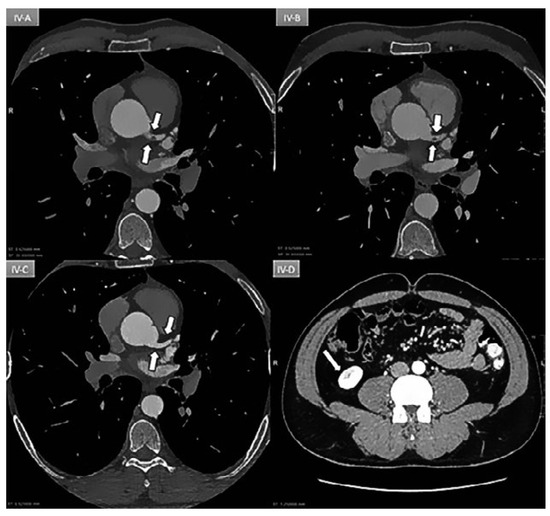

Direct His bundle pacing has recently attracted interest as a more physiological alternative to right ventricular or biventricular stimulation. The advent of new tools has facilitated the implantation procedure. This report relates our initial experi...